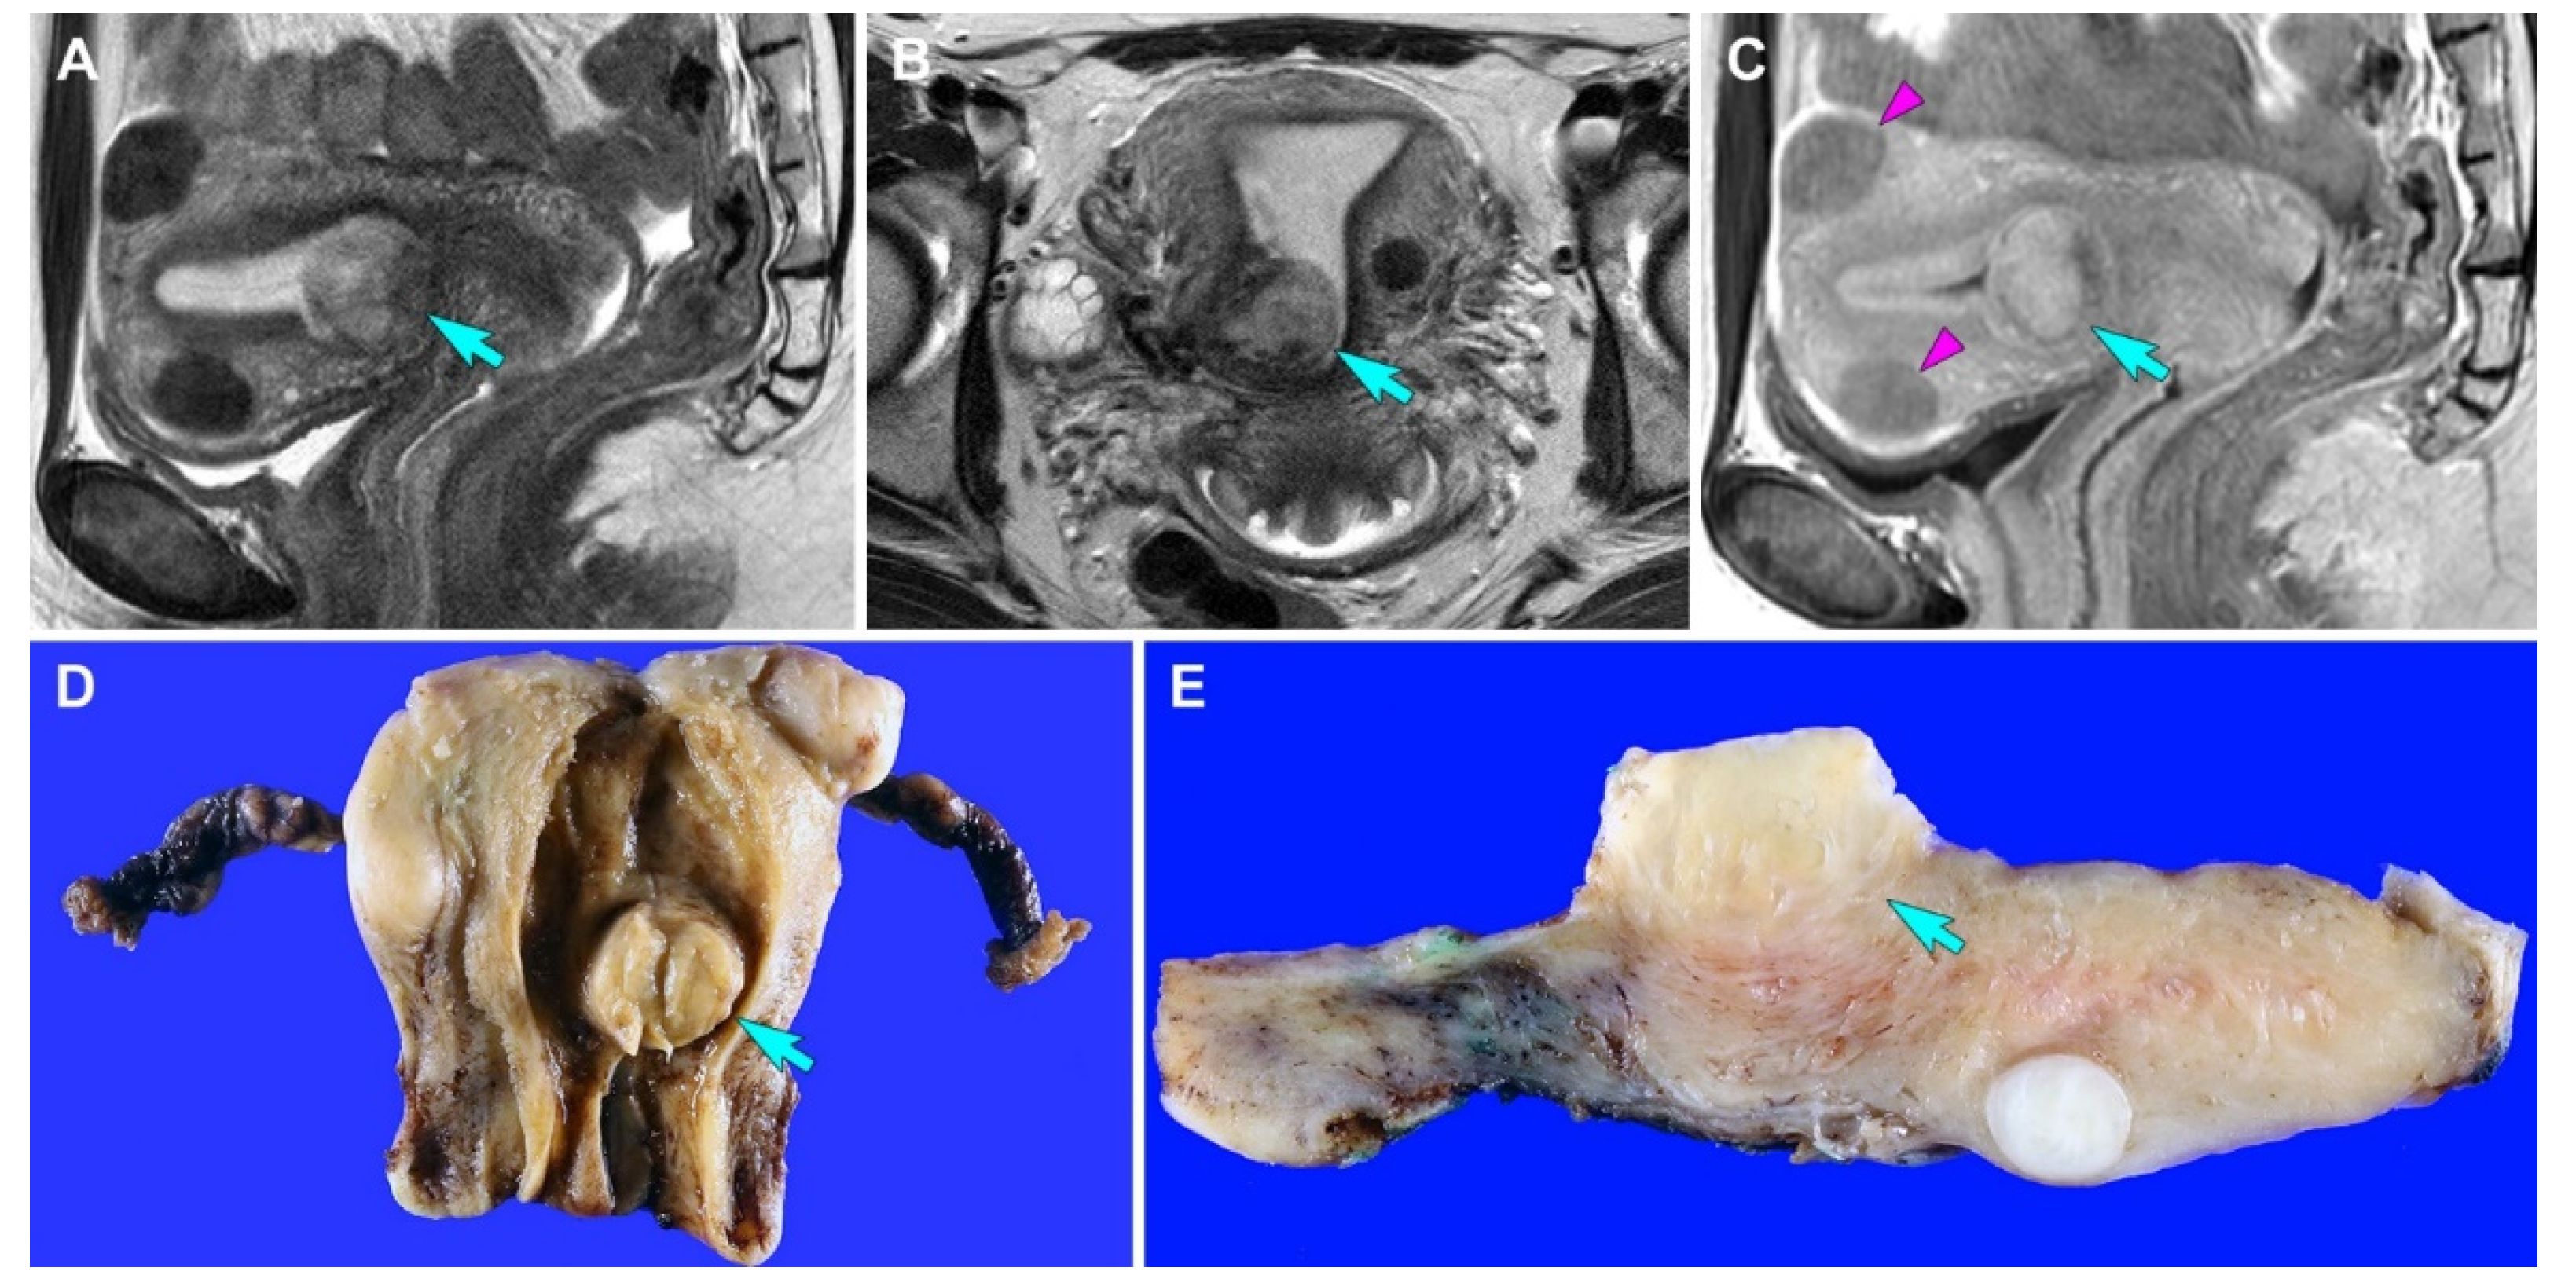

3.1. Case 1: Primary ASPS of the Uterine Corpus

3.1.1. Clinical Presentation

3.2.1. Clinical Presentation

3.2.2. Pathological Findings